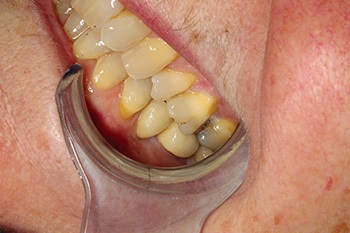

Fig. 1: Pre-op with missing molar.

Fig. 2: Pre-op occlusion.